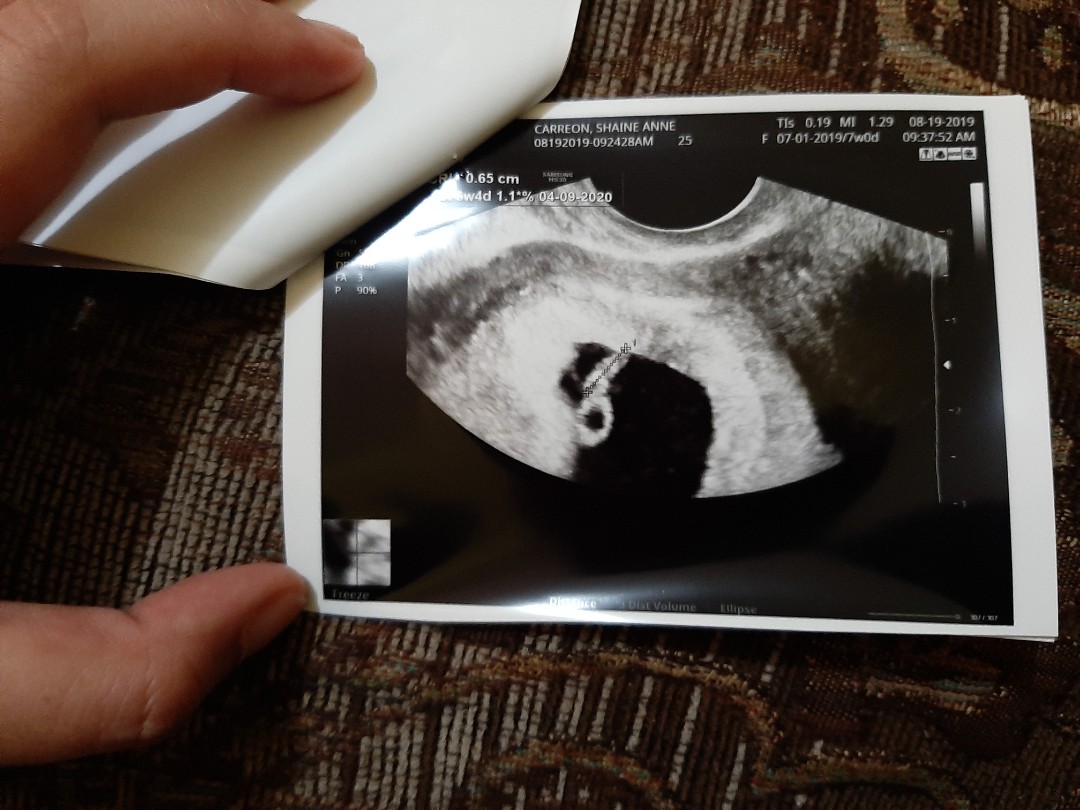

Mga momshie..tanong ko lang po..pag po two line is positive?tanong ko lang kasi nagpa ultrasound po ako kanina..para sana makita kung ilang weeks na akong buntis..pero nakakapag taka dipa makita si baby sa ultrasound..so nag pt po ulit ako ng dalawa pang beses..at ganyan parin po ang lumabas dalawang line..naka tatlong pt po ako..at lahat positive..ang sabi po ng ob..nauuna daw po talaga ang pt kesa sa ultrasound..sa pt positive na pero sa ultrasound wala pa..so ang tanong kopo buntis poba talaga ako?ang sabi po hintayin kopo ang 2weeks pa para makita na si baby..masyado daw po kasi maaga ang pag ultrasound ko..so ano po sa tingin nyo?pakisagot po please..nakaranas din poba kayo ng ganito?salamat po

T Ako po 6weeks na nakita na po thru trans vaginal po..

Ako sakto 7 weeks ko sya nakita at sobrang liit pa talaga nya.